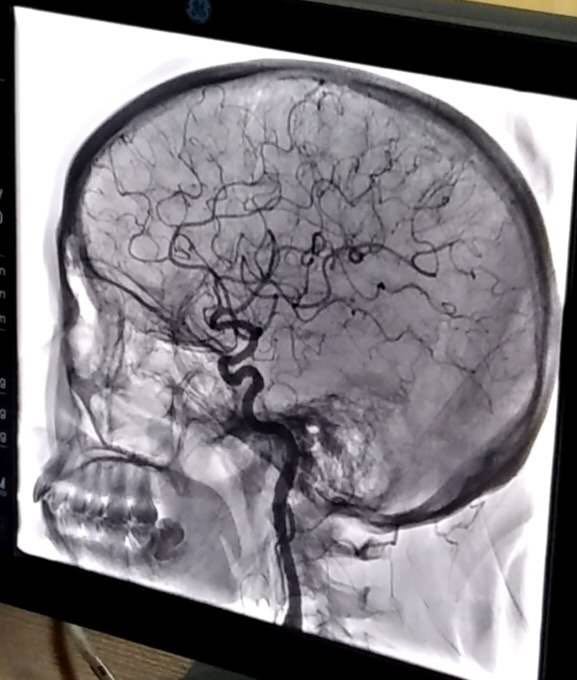

患者青年女性,發(fā)作性頭暈多年,輾轉(zhuǎn)各地醫(yī)院進(jìn)行診治,均未明確具體原因。經(jīng)我院給予全腦血管造影術(shù),發(fā)現(xiàn)病變血管,明確病因,為以后的診治確立了正確的方向。首次開展此項(xiàng)檢查,對(duì)我們醫(yī)護(hù)人員是一個(gè)重大考驗(yàn),從術(shù)前準(zhǔn)備到成功完成檢查再到術(shù)后護(hù)理,我們醫(yī)護(hù)人員能夠熟練掌握流程,嚴(yán)格遵守各項(xiàng)操作規(guī)范,使患者快速有效完成檢查?;颊弑硎緦?duì)治療效果很滿意。

全腦血管造影術(shù)是在數(shù)字減影血管造影(DSA)系統(tǒng)的支持下,采用血管內(nèi)導(dǎo)管操作技術(shù),通過(guò)選擇性造影、栓塞、擴(kuò)張成形、機(jī)械清除、藥物遞送等具體方法,對(duì)累及人體神經(jīng)血管系統(tǒng)的病變進(jìn)行診斷和治療。它是一種微創(chuàng)臨床技術(shù),為許多腦與脊髓血管疾病開辟了新的思路和治療途徑。既可以獨(dú)立解決許多腦血管疾病,又可以和傳統(tǒng)的開放手術(shù)、放射治療等巧妙結(jié)合,使原來(lái)無(wú)法或難以治療的疾病得到滿意療效。它不但能提供病變的確切部位,而且可以清楚地了解病變的范圍、嚴(yán)重程度、與周圍血管的關(guān)系等細(xì)節(jié),對(duì)確立治療方案指導(dǎo)進(jìn)一步治療有重要意義。

全腦血管造影術(shù)主要是治療腦與脊髓血管病,在腦腫瘤、脊柱腫瘤等疾病的治療也有涉及。治療方向包括1.缺血性腦血管?。耗X動(dòng)脈狹窄,急性或慢性腦動(dòng)脈閉塞,顱內(nèi)靜脈竇血栓等。2.出血性腦血管?。耗X動(dòng)脈瘤,腦動(dòng)靜脈畸形、動(dòng)靜脈瘺、脊髓-脊柱血管畸形等。3.腦-脊髓脊柱腫瘤類:富血運(yùn)腫瘤術(shù)前造影評(píng)估與栓塞,惡性腦腫瘤動(dòng)脈內(nèi)超選擇性化療等